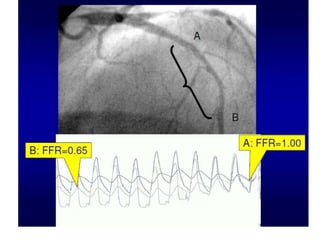

FFR

Definition

• It is ratio of driving pressure of

microcirculation flow distal to stenosis to

driving pressure proximal to stenosis in a

maximally dilated microvascular resistance

vessels (R2).

• FFR = Pd/Pa0

Fractional flow reserve

• Equivocal or intermediate lesions , and in the absence of

demonstrated ischaemia, decision making based on

angiography alone is challenging.

• FFR has been extensively described and validated as a

technique capable of identifying functionally significant lesions

• FFR value below the threshold value of 0.75 corresponds to

inducible ischaemia

• Studies have shown that a strategy of revascularization based

on FFR results in this context is acceptable.